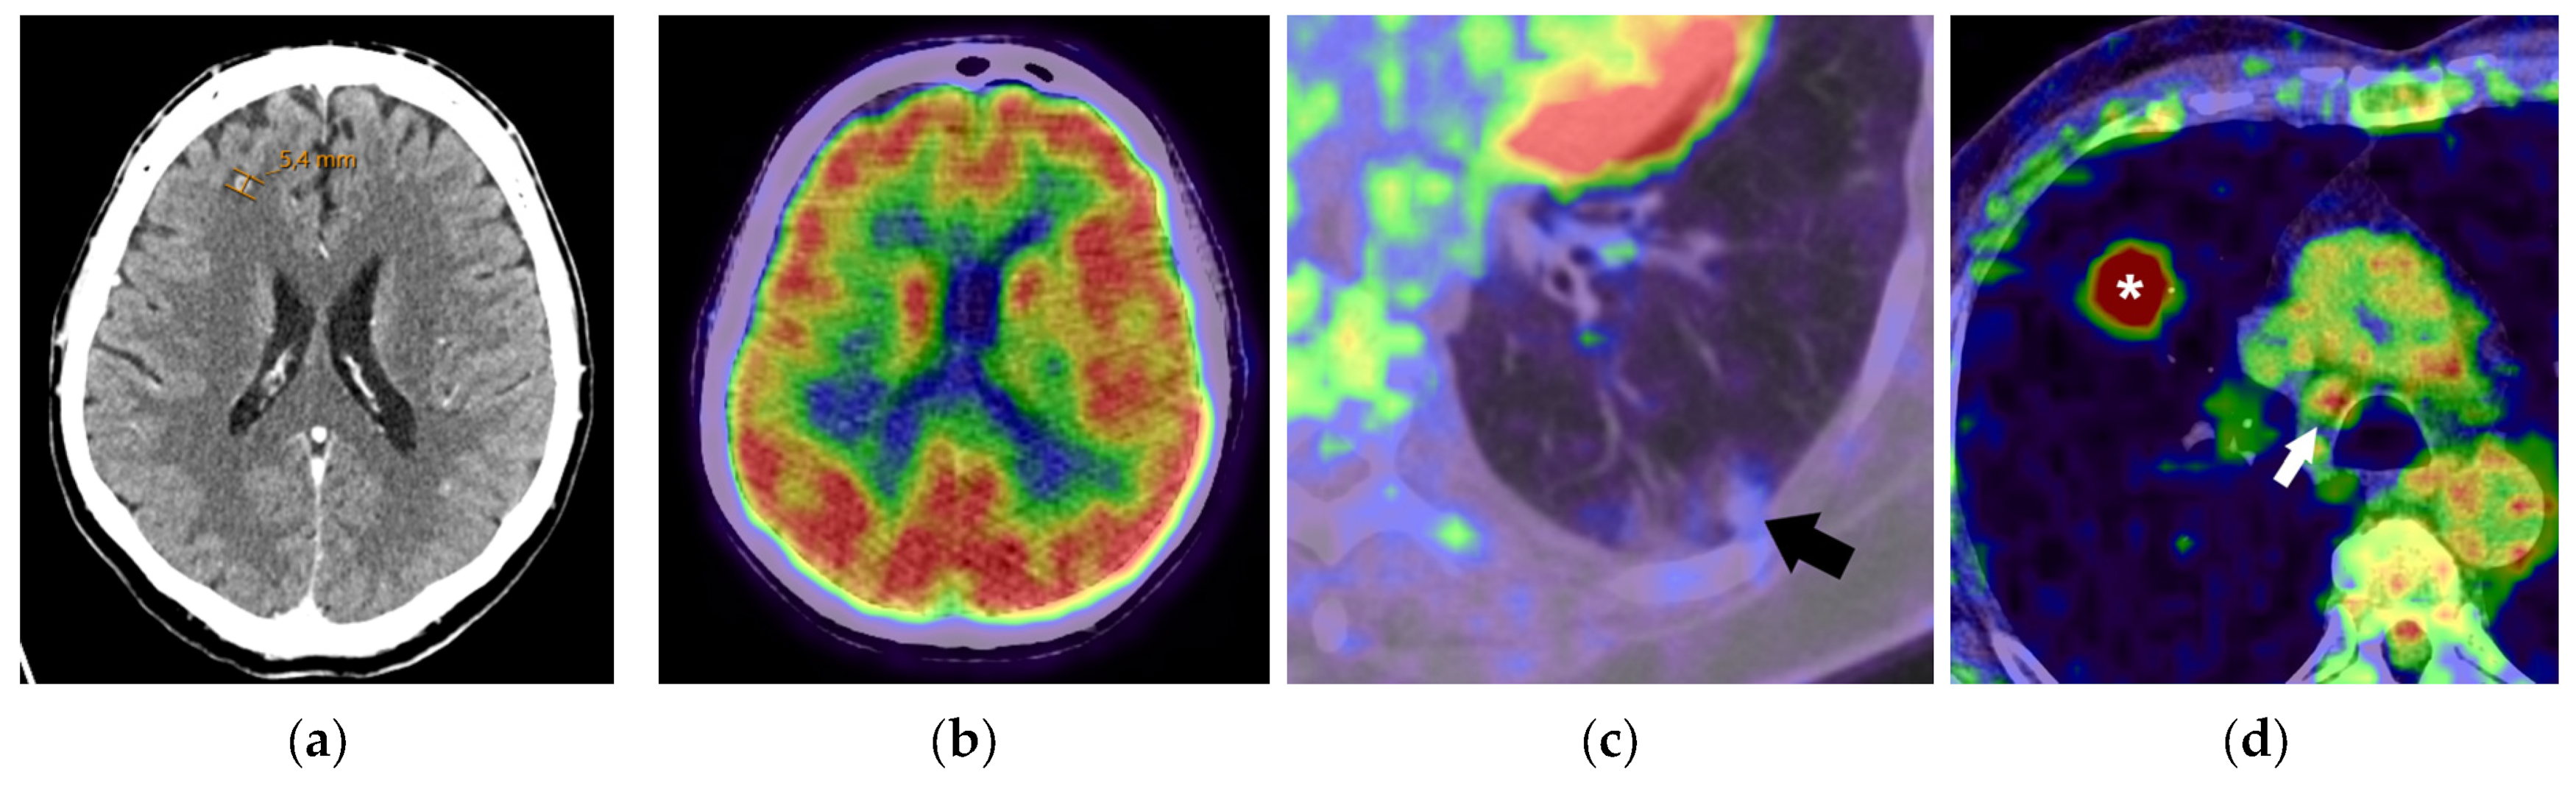

- Contrast-enhanced CT is a fundamental tool in the diagnosis and staging of lung cancer, but its sensitivity for detecting local invasion and regional or distant metastases can be suboptimal compared to advanced modalities.

- FDG PET/CT offers improved sensitivity and specificity over CT but is not effective for cancers with low FDG avidity or for the detection of brain metastases. PET/CT can also produce false positive results in conditions like infections or inflammatory diseases that are FDG-avid.